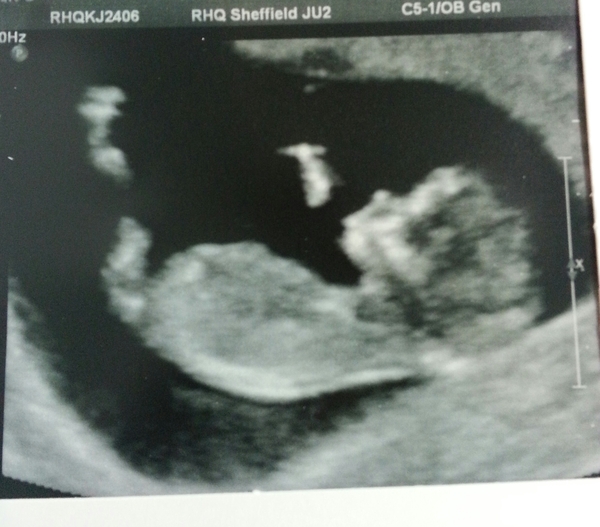

12+4 - one super wriggly bean due 3rd January! Grin

Just Shagging Grads Thread 9 - Roll Up, Roll Up all you graduated Viroids!

Beautiful picture. :-) How lovely. Xx